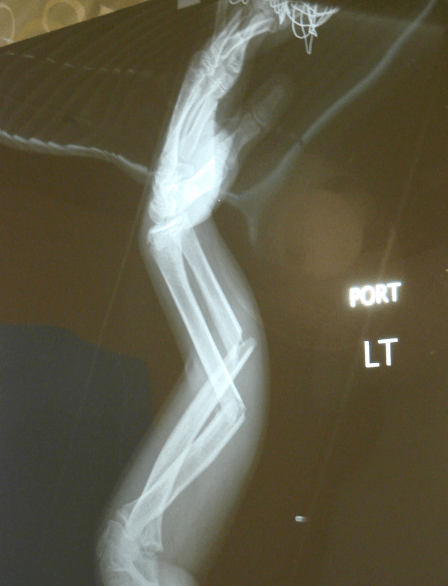

4- One person posted an intriguing X-ray, saying, “X-Ray from when I broke my arm in 2008.” The image offers a glimpse into the inner workings of a healing fracture.